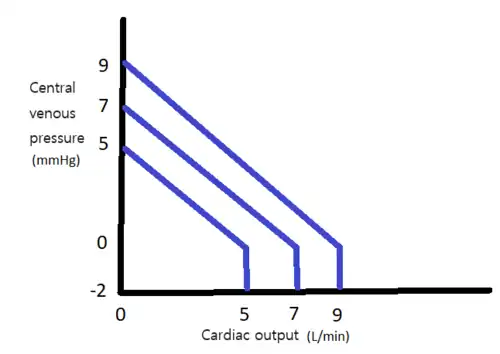

The capacitance, also known as compliance, of the arterio-vascular channels that carry the blood also controls cardiac output. As the body's blood vessels actively expand and contract, the resistance to blood flow decreases and increases respectively. Thin-walled veins have about eighteen times the capacitance of thick-walled arteries because they are able to carry more blood by virtue of being more distensible.[69]